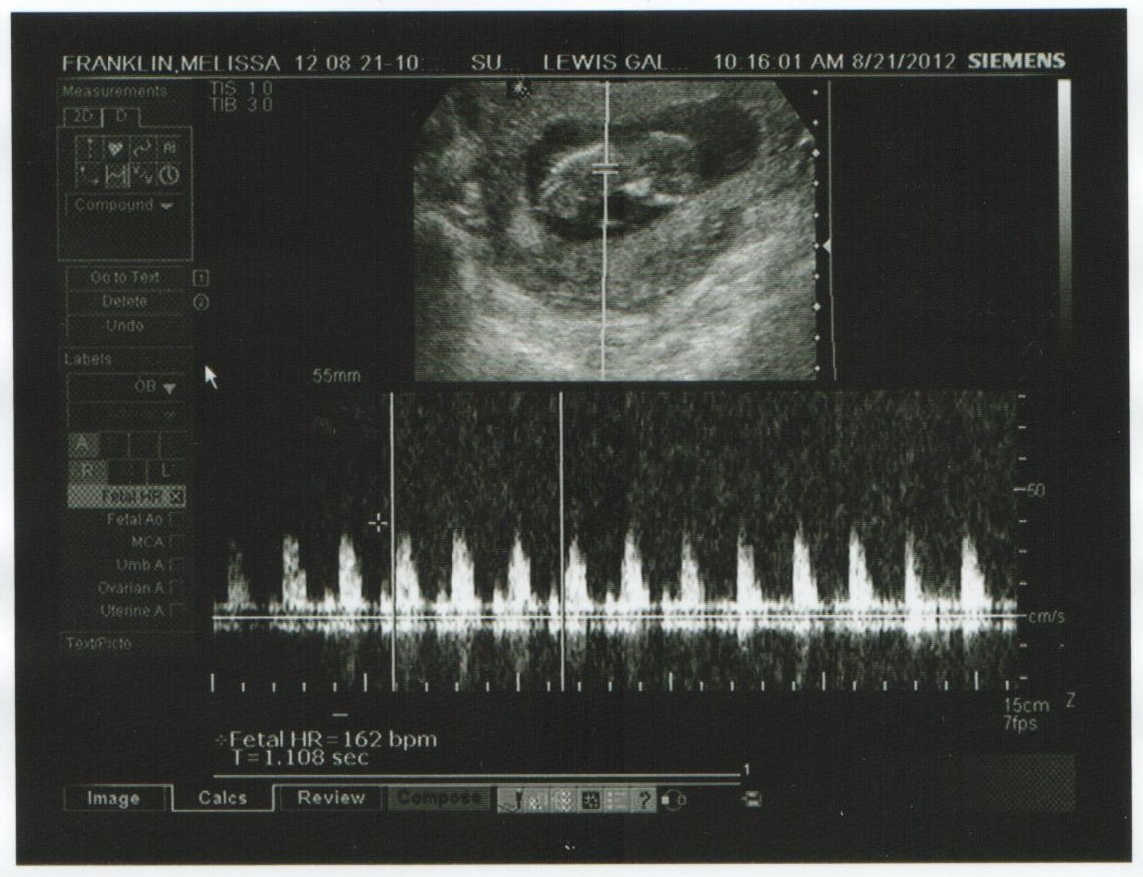

No one will be as shocked as we were!  I can hardly believe we are going to have another baby.  Yes, it's true.  March 3, 2013, is the due date.  Tj came home June 4!  We found out right after we came home from our Germany trip.  The kids weren't home yet and I took a couple of tests.  The dollar test was negative and I thought that it was wrong, so we bought a more expensive one and took it just a few hours after the dollar test - and yep - we got a positive.  Moving was soooo hard for me.  I think it must have had something to do with the hormones.  I cried all the time, I slept all the time, and I felt sick all the time.  I'm sure the kids wondered what in the world was wrong with me.  We had to wait for what seemed like forever to be able to go to the doctor.  We had to wait for insurance to get switched over, wait for a referral to an OB (which seems crazy that I had to do that!), and then wait for an available appointment with the OB.  FINALLY we got to go to the doctor on August 22.  When you find out your pregnant on June 22, having to wait until August 21, to go to the doctor seems like a lifetime!  We told the kids the night of August 23.  We video taped it and I'm so glad we did!  Their reactions were just priceless!  We had ultrasound pictures of the baby with one saying "hi Tyler" and the other "hi Brenalee."  We gave them those pictures and asked if they knew what it was.  At first they thought it was themselves.  We said no, guess again.  Then they got all excited and said "Aunt Steph is having a baby!!!"  Ummmm, no - that would be bad seeing as how she's not married quite yet!  Finally we just had to tell them it was their baby brother or sister.  Brenalee was so excited - she was jumping up and down, squealing.  It was great.  Tyler just sat there and told us we were making this up.  He honestly didn't believe us until the next day!

So, now with everyone knowing and being excited, seeing my baby opening and closing it's little mouth, kicking and moving on the ultrasound, how can I not be excited??  The fear is gone, and I just feel happy and I can't wait to meet this special little person!